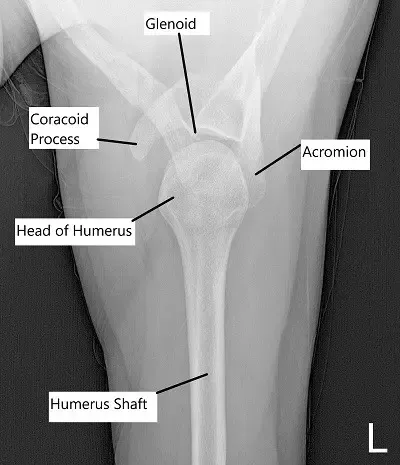

Vista axial del hombro izquierdo.